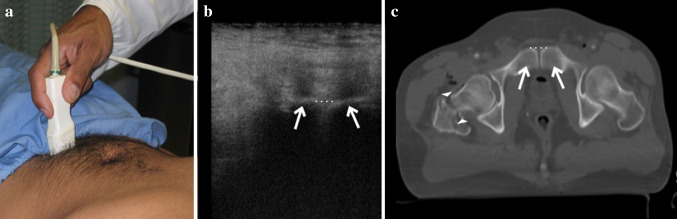

Fig. 1.

a Example of a transverse scan of the pubic symphysis performed with a high-frequency linear probe; b, c anatomical representation of the pubis at US transverse scans (b) and at CT axial scan of the pelvis (c) with evidence of branched (b, c, arrows) and not diastased symphysis (b, c, dotted line) in patient with femoral right neck fracture (c, arrowheads)

The FAST–PLUS exam was first carried out with a low-frequency probe (3.5–5 MHz convex transducer) for better penetration of tissues in the abdominal cavity, to exclude hemoperitoneum, according to the well-known FAST protocol (pericardial view; right and left flank view; pelvic view). It was subsequently performed again with a high-frequency probe (15–4 MHz linear transducer) for the evaluation of both hemithorax (i.e. the pleura) to exclude pneumothorax or hemothorax, according to the extended-FAST version and finally with the same high-resolution linear probe, the pubic symphysis was scanned with a transverse section (Table 2). Both probes are ready to use in the same US machine (MyLab™25, Esaote SpA, IT) without time-consuming adjustments. Measurements of pubic SW were made between the pubic tubercles on the transverse scan (Fig. 1). A pubic SW > 2.5 cm in transverse diameter was considered positive for unstable OB pelvic fracture. CT images were obtained with a multidetector row CT scanner with 64 detector rows (Somatom Sensation, Siemens Medical Systems, Erlangen, Germany) after intravenous contrast media administration to exclude active bleeding.